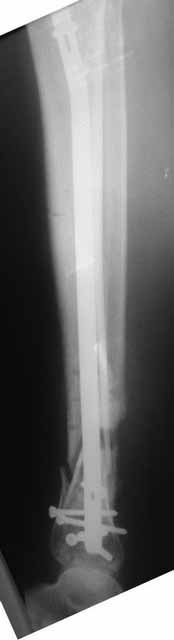

Да уж! Ни один из 3-х оперативных методов предшествующего лечения не был исполнен правильно. Везде был серьезный брак. Хотя любой из методов вполне мог бы и должен был бы привести к сращению,...если бы, да кабы.. В результате имеем то, что имеем. Что делать? Во-первых - подумать. Во-вторых - еще раз подумать. В третьих - еще больше подумать.

Если нет данных за инфекцию в зоне перелома мы бы аппараптом дозированно устранили деформацию и, не удаляя дистальный фрагмент сломанного гвоздя, закрыто, после рассверливания заштифтовали бы достаточно толстым и надлежащей длины гвоздем.... Если есть спицевой остеомиелит, то также сначала аппарат, затем рассверливанме и цементный спейсор с а\б согласно посевам, через 2-3 недели удалить спейсор, повторно рассверлить и заштифтовать штифтом, возможно покрытым антибиотиком. А если Вы умело владеете техникой Илизарова, и больной согласен, можете оставить аппарат как окончательный метод фиксации....

В любом случае, если нет инфекции в зоне несращения и кость жизнеспособна, упаси Вас Бог что либо открывать и добавлять свободную костную пластику. Надо попытаться все сделать закрыто. Если откроете, то через пару месяцев, а может и раньше, все закончится резекцией и значительно большей чем 4 см...

Боюсь, кусок гвоздя в канале будет сильно мешать, так что мы бы открыли бы над ним передне-медиальную кожно-надкостнично-костную "крышку", и убрали. То есть не скелетировать чтобы кость даже вдали от несращения.

А так - согласен с Алексеем, аппаратная репозиция (если тугоподвижность - то за несколько дней), зону несращения не открывать, рассверлить, помыть, стержень с антибактериальным цементным покрытием.

(АС) Если нет данных за инфекцию в зоне перелома мы бы аппараптом дозированно устранили деформацию и, не удаляя дистальный фрагмент сломанного гвоздя,

(АЧ) Боюсь, кусок гвоздя в канале будет сильно мешать, так что мы бы открыли бы над ним передне-медиальную кожно-надкостнично-костную "крышку", и убрали. То есть не скелетировать чтобы кость даже вдали от несращения.

Подвинуть новый гвоздь обломок сможет, а вот блокировать может не дать. Мы и отломок гвоздя попробовали бы удалить закрыто.

Как-то вот нет уже желания открываться в зоне ложного сустава. Мы бы

попытались сделать закрыто. Винт в дистальном отломке удалить через прокол.

Кусок гвоздя оставить. Новый гвоздь (солидный), возможно с покрытием.